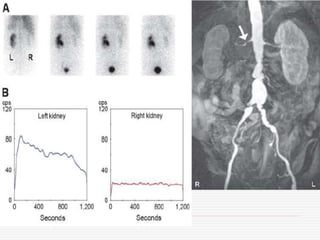

Decreased graft function 5/12

post-transplant, renogram

showed an OIH accumulation

within normal limits, normal peak,

but delayed elimination

1-min images reveal tracer

retention in parenchyma without

outflow impairment – suggesting

potential CNI toxicity